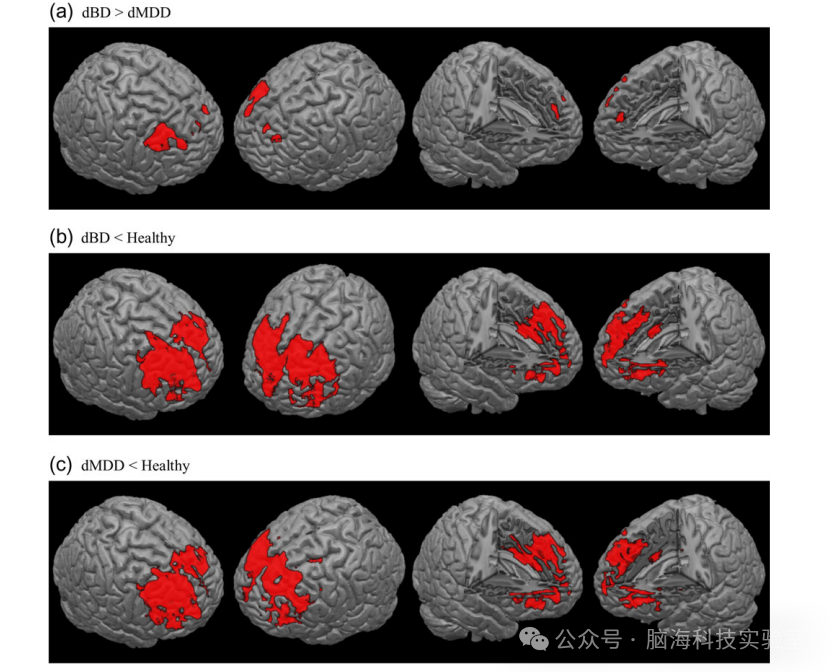

在分析中发现扫描仪对结果有显著影响,尤其是在右侧杏仁核/左侧丘脑和左侧中额回区域。这些区域受扫描仪影响的面积占所有感兴趣区域(ROI)的约62.6%。研究将这些区域作为掩膜,以排除扫描仪效应对后续分析的干扰。与单相抑郁障碍患者相比,双相抑郁障碍患者的DLPFC和ACC的灰质体积显著减少。具体而言,右侧DLPFC(体素坐标:x=30, y=33, z=48;体素数k=886;t值=6.60;校正后P值=4.80×10⁻⁷)和左侧DLPFC(x=-25.5, y=49.5, z=31.5;k=75;t=5.46;校正后P值=2.78×10⁻⁴)的灰质体积减少显著。此外,右侧ACC(x=3, y=49.5, z=21;k=55;t=5.58;校正后P值=1.55×10⁻⁴)和左侧上内侧额回(x=-4.5, y=49.5, z=24;k=98;t=5.14;校正后P值<0.001)也表现出灰质体积减少。这些差异在不同扫描仪之间具有显著性和较大的效应量,表明这些区域的灰质体积差异在dBD和dMDD之间是可靠的。

dBD患者与健康对照相比,右侧ACC和中额回(x=3, y=49.5, z=19.5;k=12318;t=11.5;校正后P值<0.001)以及左侧额下回三角部(x=-39, y=10.5, z=25.5;k=44;t=4.9;校正后P值=0.003)的灰质体积显著减少。dMDD患者与健康对照相比,右侧中额回和内侧额回(x=34.5, y=49, z=28.5;k=12841;t=9.9;校正后P值<0.001)、左侧额下回眶部和三角部以及左侧岛叶(x=-37.5, y=28.5, z=33;k=348;t=9.7;校正后P值<0.001)以及左侧中额回(x=-24, y=-3, z=48;k=156;t=4.8;校正后P值=0.005)的灰质体积显著减少。

图1基于体素的形态测量学中不同诊断的灰质差异。